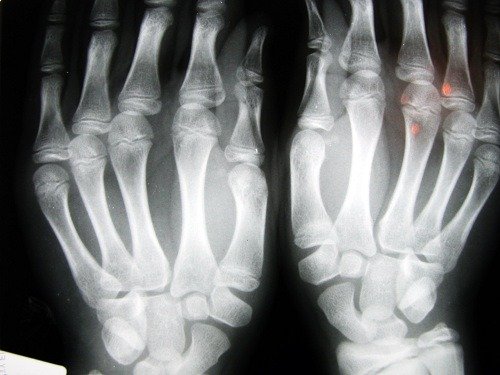

Knogleskørhed er en knoglesygdom, der forårsager et fald i massefylden af knoglemassen. Denne sygdom er kendetegnet ved porøse knogler. Ved at øge størrelsen af de indre celler i knoglerne bliver de skøre og brækkere lettere.

Frakturer forekommer ofte i håndledene, og også i hofternes hvirvler. Dette er det mest alvorlige brud, fordi det indebærer øjeblikkelig kirurgisk indgreb og alvorlige konsekvenser for patientens helbred.